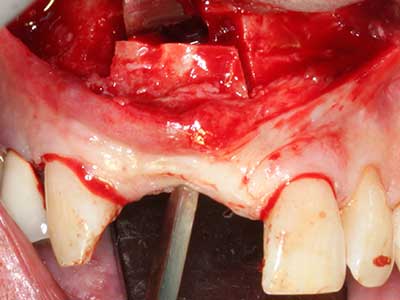

Aplicación: Partición ósea / Cortical Split

El tejido óseo no solo tiene un contenido puramente mineral, sino que también presenta una importante proporción de fibras de colágeno. Esto no solo garantiza una buena resistencia a la presión, sino también una cierta flexibilidad, que puede aprovecharse para la realización de aumentos. En la plastia de expansión clásica a efectos de una partición ósea, la cresta maxilar atrofiada se divide en su eje longitudinal y, tras alcanzar una profundidad de osteotomía suficiente, se extiende con cuidado (fig. 13-16), en un caso ideal sin desperiostizar de forma visible el maxilar (Brugnami, Caiazzo et al. 2014, Stricker, Fleiner et al. 2014). Los sistemas de tornillos y placas con distancia de expansión creciente han demostrado su eficacia para distanciar entre sí las dos tablas óseas por debajo del umbral de rotura. Por regla general, se requieren anchuras de hueso residual de al menos 3 a 4 mm (Chiapasco, Zaniboni et al. 2006) para garantizar una flexibilidad y una cobertura ósea suficientes de los implantes que van a incorporarse. En caso necesario, una osteotomía de descarga vertical unilateral o bilateral puede mejorar la flexibilidad. Como alternativa a la técnica clásica se ha descrito una combinación con otras técnicas de aumento, sobre todo en la parte bucal.

Con el uso de sierras piezoeléctricas la división se efectúa de forma especialmente cuidadosa y sin pérdidas importantes de las dimensiones, por lo que no se han encontrado diferencias significativas entre los implantes realizados en el maxilar dividido y en la cresta alveolar no deficitaria (Chiapasco, Zaniboni et al. 2006, Danza, Guidi et al. 2009). No obstante, precisamente en la partición profunda y limitada de forma local, es preciso asegurarse de que exista una adecuada irrigación por agua para evitar que se produzcan sobrecargas térmicas en las áreas de osteotomía apical.

Fig. 13: En este paciente de 52 años con una anchura del hueso residual del maxilar inferior de 4 mm, hay que asegurarse de que exista refrigeración por agua adecuada durante la partición del hueso.

Fig. 14: Incorporación de cuatro implantes RSX cónicos (Bego Implant Systems, Bremen).